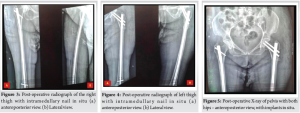

Recognizing the bilateral AFFs and the imminent risk of a right-sided fracture, prophylactic intramedullary nailing was performed on the right femur (Fig. 3), based on the current clinical evidence. This approach also facilitated positioning for subsequent fracture reduction and reconstruction nailing of the left femur (Fig. 4), conducted 2 days later. The postoperative course was uneventful. Bisphosphonate therapy was discontinued, and the patient was started on teriparatide injections, calcium, and vitamin D supplementation. After satisfactory post-operative X-rays (Fig. 5), full weight-bearing mobilization with walker support was initiated.